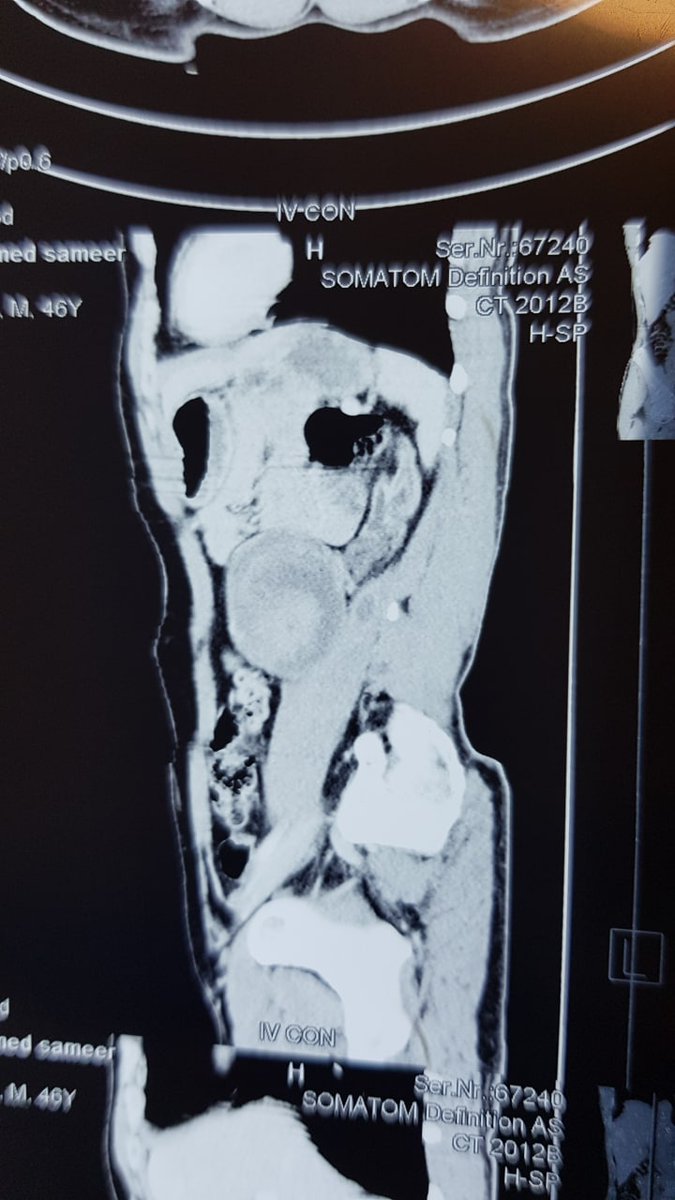

20 days old male presented with antenatal u\s bilateral pcs dilatation. *U/s one week after birth showed below. what is the best MX??

20 days old male presented with antenatal u\s bilateral pcs dilatation.

*U/s  one week after birth showed below.

what is the best MX??